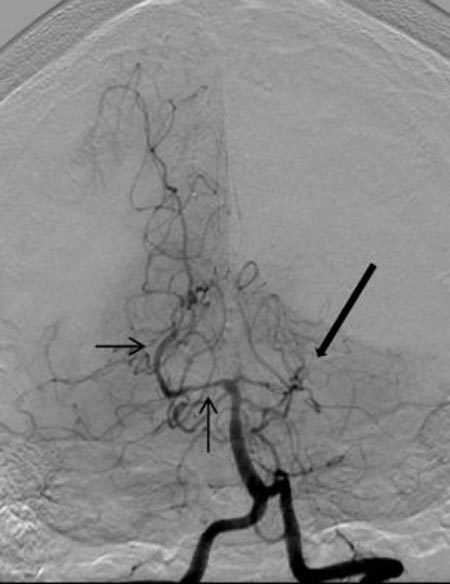

Mũi tên lớn trong bức ảnh cho thấy một điểm tắc nghẽn ở một trong các động mạch não của cô M.P. Mũi tên nhỏ hơn chỉ sự co thắt và giãn nở ở một động mạch khác. Ảnh: Neurology |